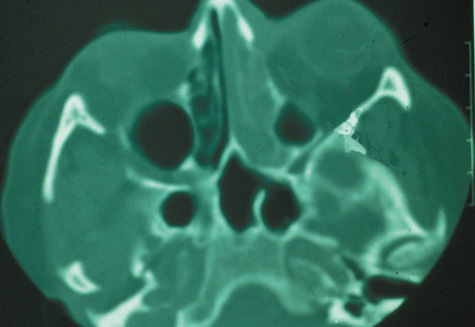

CT is particularly useful for imaging orbital and subperiosteal abscesses. Because the periorbit is not adherent to the orbital walls except at the suture lines, an abscess lifts the periorbit, creating a convexity in the orbital periosteum (Fig. 16). Usually subperiosteal abscess formation occurs adjacent to the involved sinus,25,64 but occasionally it occurs at a remote location such as the superolateral orbit.65 Gas may be found within a subperiosteal abscess or within the orbit, arising either from gas-forming bacilli or free communication with sinus air or from prior trauma (Fig. 17). 57,66 CT cannot accurately predict whether a subperiosteal mass represents exudate, inflammatory transudate, or hematoma.67,68

Fig. 16. Computed tomography showing subperiosteal abscess formation. Note elevation of orbital periosteum and convexity as pus elevates periorbit from the medial orbital wall.

Fig. 17. Intraorbital gas in a 58-year-old patient with orbital cellulitis from a left frontal sinus mucocele. Gas appears as an area of complete radiolucency on this computed tomographic image.

A subperiosteal abscess may rupture or invade the periorbit, resulting in an orbital abscess. This may or may not be contiguous with the subperiosteal collection on CT. There may be gas or air–fluid levels within the mass.51,56,58,59 An orbital abscess may present as an enhancing ringlike peripheral mass that can be either heterogeneous or homogeneous (Fig. 18).

Fig. 18. Orbital abscess. A. Computed tomography of an orbital abscess presenting as an enhancing intraconal mass on right side. B. T1-weighted image. C. T2-weighted image. Note area of high signal corresponding to abscess.